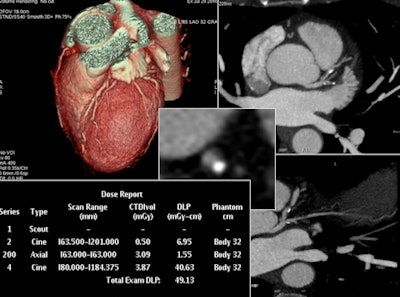

In the final part of the study, Matkevich et al analyzed the image quality of low-dose CT examinations of the heart and coronaries, chest, and carotids. According to the authors, good diagnostic quality was maintained despite a reduction in radiation exposure, this achieved with decreased tube voltage (80 kV to 100 kV) and tube current in combination with iterative reconstruction (ASIR and MBIR).

Sinitsyn is not surprised the study results were in line with other countries in Europe because Russian hospitals use the same scanners, follow the same protocols, and have the same strict guidelines governing CT indications and dose. The Moscow center has been performing low-dose coronary CT for five years, and with discussion about lung cancer screening and pediatric CT imaging increasingly in the spotlight, dose reduction has become a more urgent topic.

Low-dose CT for complex scanning is increasingly feasible, thanks to decreased tube voltage and current, in combination with iterative reconstruction, according to Sinitsyn. This reconstructed image from low-dose coronary CTA was achieved with reduced tube voltage of 80 kVp and automatic tube current modulation.He explained the department website regularly received letters from worried patients, particularly women, who typically discover postscan they were already pregnant when undergoing the exam. The Moscow group wanted to show that radiation exposure from CT in the hospital was compatible with levels in other countries and within acceptable limits.